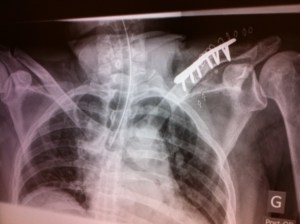

En 2012, j’ai rejoint le club des éclopés du vélo suite à une bonne chute. Clavicule gauche fracturée à deux endroits et commotion cérébrale. Après un mois de convalescence, j’ai commencé à ressentir des engourdissement dans ma main et progressivement, mon avant-bras s’est paralysé. Je n’arrivais plus à boutonner ma chemise ni à couper les aliments dans mon assiette. Après de multiples examens, Tacos, Radios, etc, mon orthopédiste a finalement accepté d’opérer l’épaule et de poser une plaque pour redresser la clavicule. Ça n’a apporté aucune amélioration quand à la motricité de mon bras. Un mois plus tard, une intervention chirurgicale avec un neurochirurgien a permis de dégager mon nerf brachial qui était coincé sous une masse de tissus près de l’omoplate. Un bon six mois de réadaptation m’a permis de recouvrer 95% de mes capacités. J’ai fait l’acquisition d’un Tacx Bushido pour passer ma frustration et continuer de rouler pendant ma convalescence.